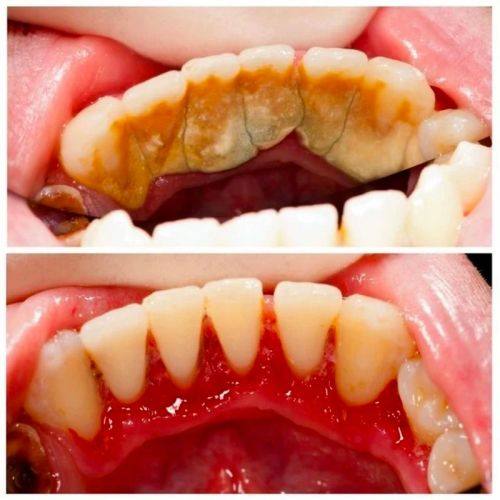

洗牙后,短期内有一些特别需要留意的地方。首先,洗牙后通常会出现局部出血的情况,这其实是正常现象,大家不用过于担心。这是因为洗牙过程中,去除牙结石等刺激物时,牙龈可能会受到一定的刺激,从而导致出血。一般来说,这种出血会在短时间内自行停止。

洗牙后一周左右,牙齿可能会出现敏感症状。这是因为洗牙去除了牙齿表面的牙结石等污垢,使牙齿表面的牙本质小管暴露出来,从而导致牙齿对冷热、酸甜等刺激更加敏感。